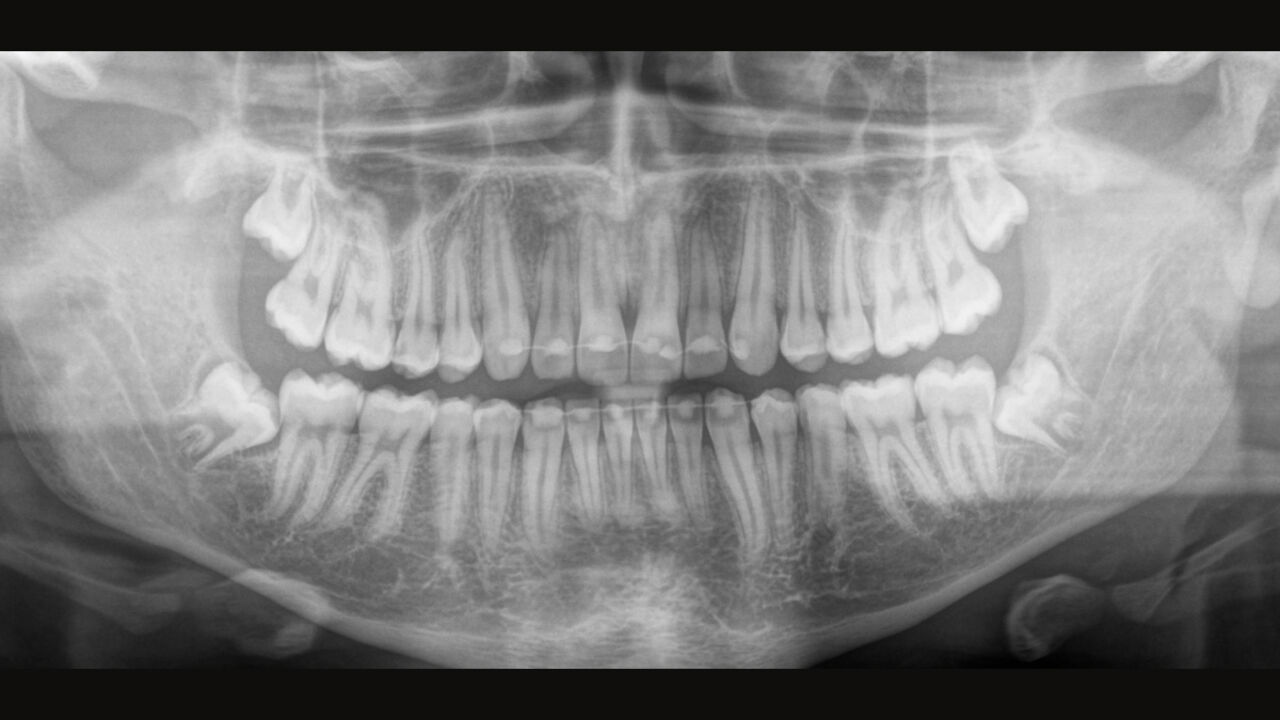

The Direct Conversion Sensor (DCS) has revolutionised the standard of panoramic imaging. X-rays are converted directly into electrical signals. Thus, there is no signal loss due to light conversion, as is the case with conventional systems. The result: images with a high level of sharpness and contrast – even at an extremely low radiation dose. For accurate diagnostic information to support targeted treatment.

The image below shows a panoramic X-ray without and with DCS technology. Using the arrow, drag the control across the image to see the difference the direct conversion sensor makes to the image quality and diagnostic possibilities.

The right focus is crucial for excellent panoramic radiographs. With the autofocus function you will automatically receive an image with the best possible sharpness in focus. Dentsply Sirona Imaging devices take several thousand individual images in one cycle and automatically identify the areas where the jaw is optimally positioned. Without any additional manual steps, these images are then displayed in a final sharp image.